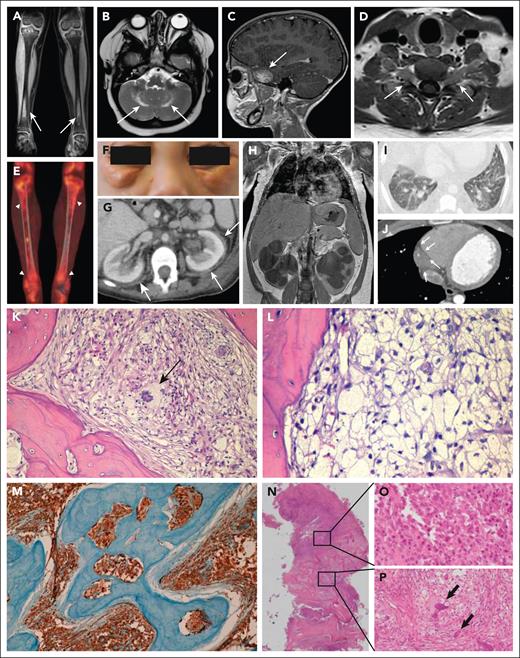

Typical ECD manifestations and bone pathology in patients with ECD and mixed ECD-LCH. (A) Coronal magnetic resonance imaging (MRI) scan showing bilateral symmetric osteosclerosis of tibial meta-diaphysis (arrows). (B) Axial MRI scan of the brain showing bilateral hyperintense lesions of the dentate nuclei (arrows). (C) Sagittal MRI scan of the brain depicting a skull base meningioma-like lesion of the greater sphenoid wing (arrow). (D) Axial MRI scan of the cervical spine showing a bilateral lesion with slight enhancement forming a dumbbell-shaped mass inside the neural foramina at C5-C6 level (arrows). (E) 18F-fluorodeoxyglucose positron emission tomography showing high metabolic activity of tibial metadiaphyseal lesions (arrowheads). (F) Periorbital xanthelasma-like lesions. (G) Axial abdominal computed tomography (CT) scan showing bilateral perinephric infiltrates (“hairy kidneys”) (arrows). (H) Coronal abdominal CT scan showing massive bilateral hydroureteronephrosis in a patient with perinephric ECD infiltrates. (I) High-resolution axial CT scan of the chest demonstrating bilateral interlobular septal thickening and ground-glass opacities. (J) Axial CT scan of the chest showing cardiac pseudotumor (arrows) developed around the right coronary artery and into the right atrioventricular sulcus. (K) Bone biopsy showing an infiltrate comprising numerous foamy histiocytes and a multinucleated Touton cell (arrow) associated with fibrosis. (L) Diffuse infiltration by foamy histiocytes. (M) Classic ECD CD68 immunostaining in a bone biopsy. (N) Mixed lesion showing an area occupied by numerous Langerhans cells with ovoid to reniform nuclei, consistent with LCH (O) and a concomitant area showing numerous foamy histiocytes and multinucleated Touton cells (arrows), consistent with ECD (P). K-L and N-P: Hematoxylin and eosin staining; M: immunohistochemical staining for CD68-PGM1. Original magnification: K, ×20; L, ×40; M, ×10; N, ×2; O-P, ×40.